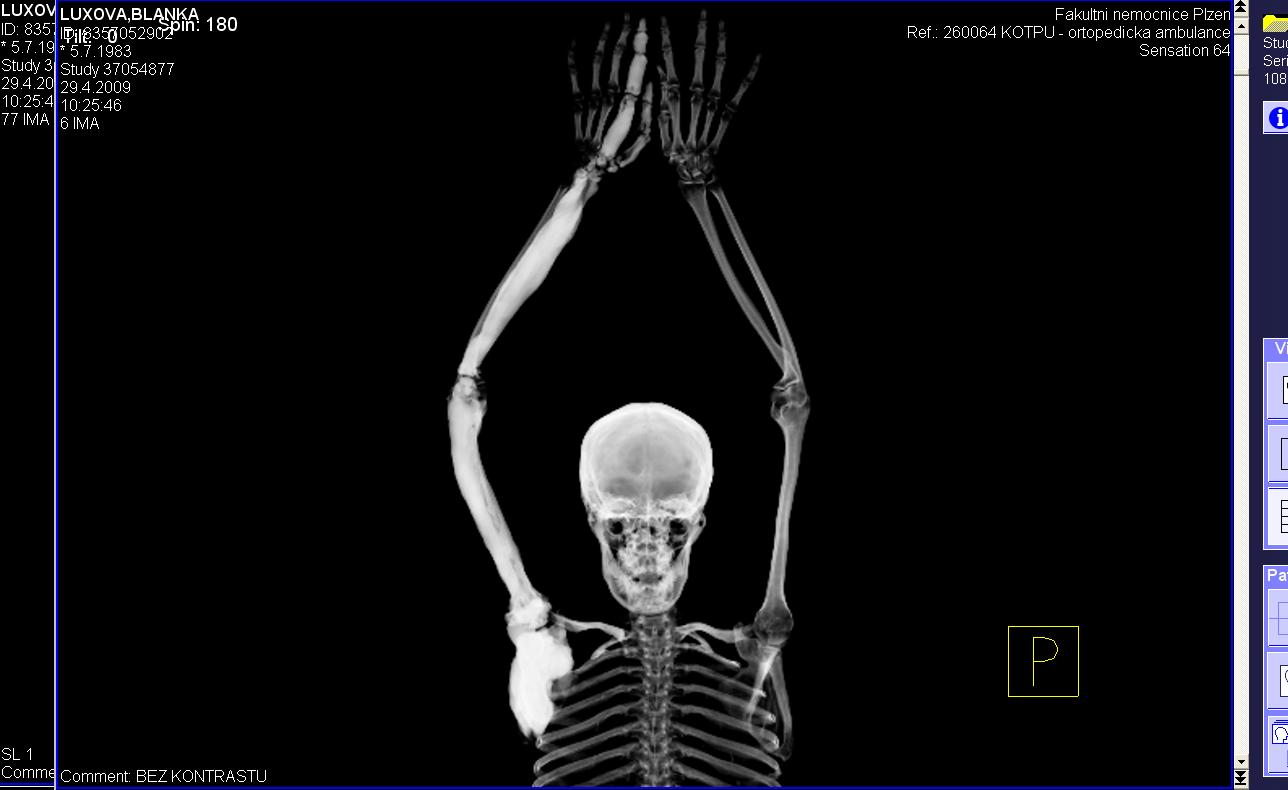

Area(s) affected:  Left arm and hand

Hi.  I am Blanka from Czech Republic. I had Melo since 10 years old, now I am 26, have one 5 years old healthy daughter, but still live in pain.

I am sending you some photos from RTG and CT and scinti scam from last month.